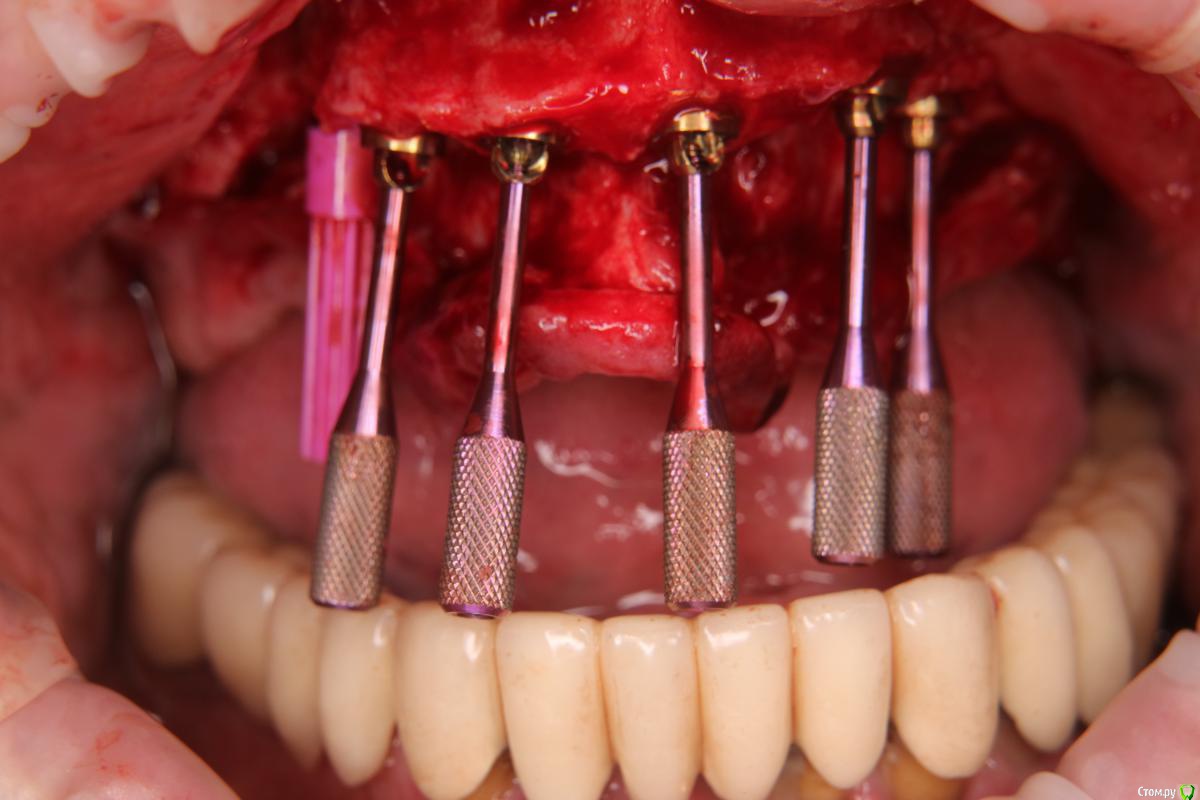

Александр07 Опубликовано 12 августа, 2020 Автор Поделиться Опубликовано 12 августа, 2020 Коллеги вот как сделали в итоге, отправляю фото 1 Ссылка на комментарий